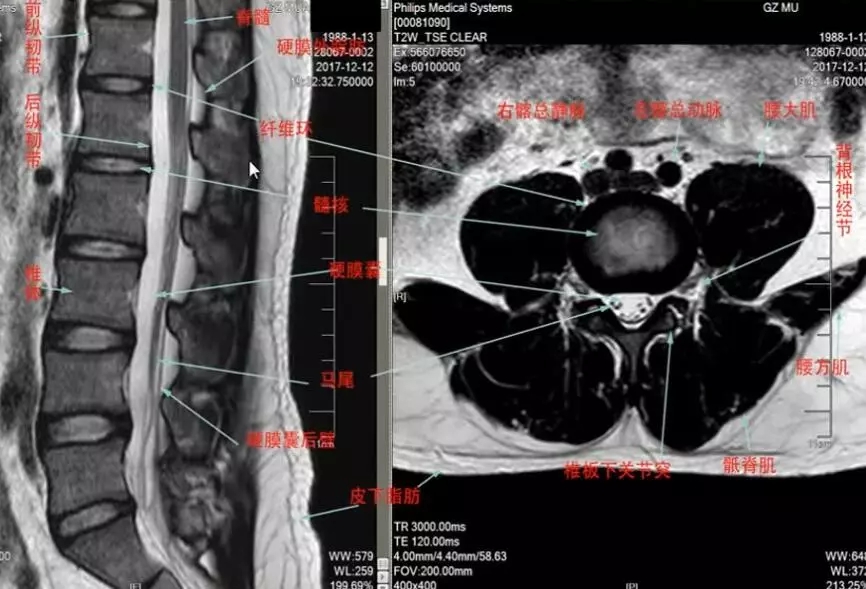

我们先来看一下脊柱脊髓mr的正常表现,可以看到前纵韧带,后纵韧带,椎体,脑脊液,脊髓,马尾神经,腰大肌,腰方肌等等